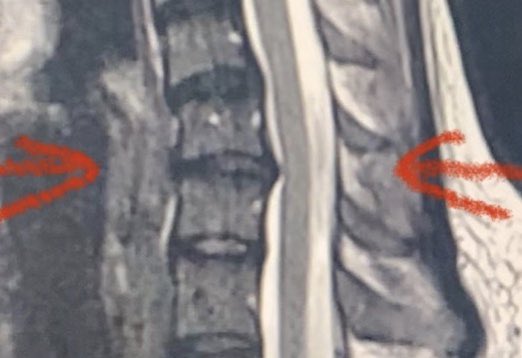

Apologies to anyone I’ve dropped the ball on over the last 2 months. Way behind on email. Been dealing with a horrible disc/nerve issue in my neck, finally got to the point of needing emergency surgery this week. Epic saga will write more on later. On the road to recovery now.